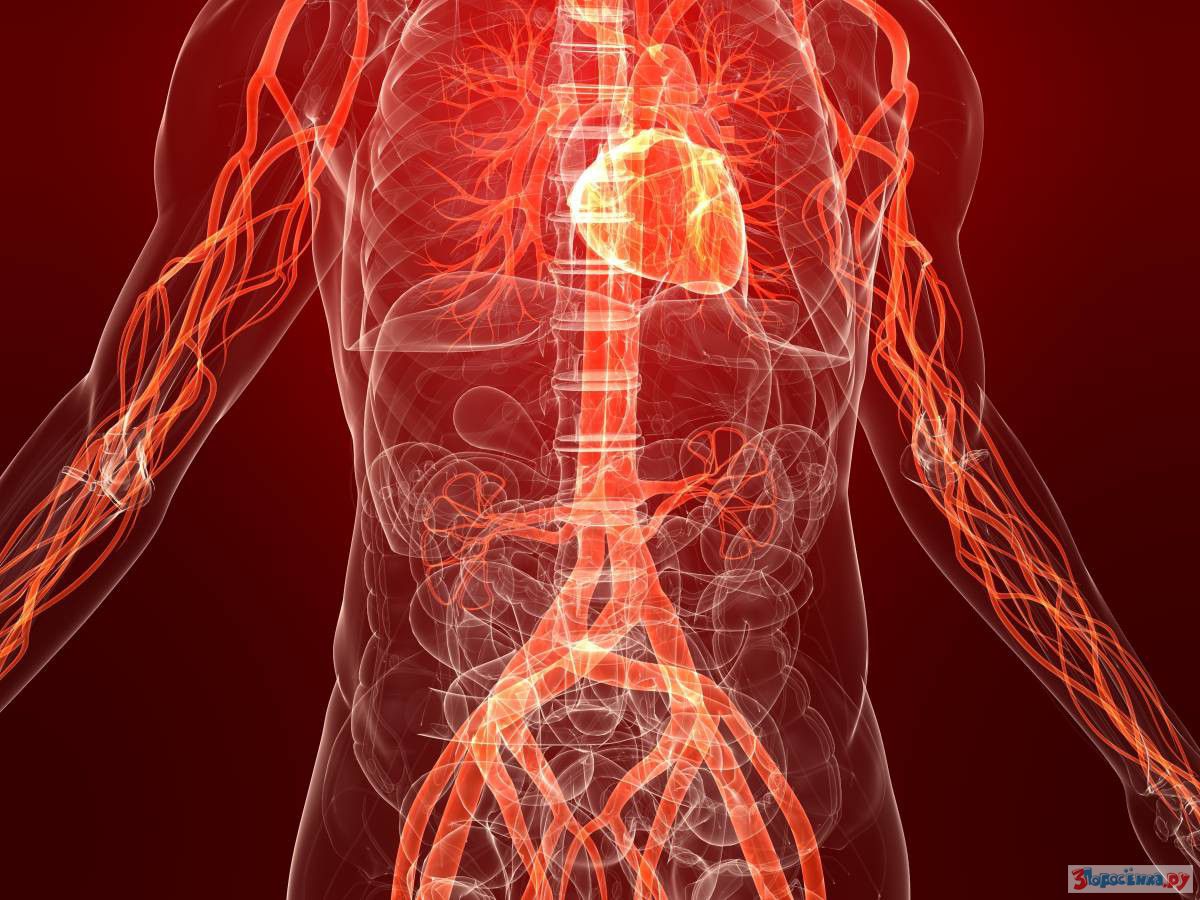

Через 20 минут восстанавливается кровообращение

Первые изменения начнутся через 20 минут - улучшается кровообращение и повышается чувствительность пальцев рук и ног.

Через неделю понижается кровяное давление

Кровяное давление начинает снижаться через неделю, что уменьшает риск инсульта, сердечно-сосудистых заболеваний, сердечной и почечной недостаточностей, и стенокардии.

Через 2 недели полностью восстанавливается кровообращение и улучшается качество половой жизни

Спустя 2 недели кровь гораздо лучше поступает к конечностям, что способствует более сильной и долгой эрекции у мужчин.